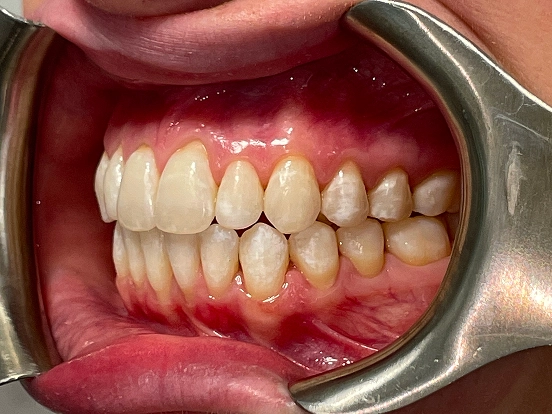

Invisalign DT

DT’s transformation with Invisalign is a perfect example of how advanced orthodontic technology can deliver incredible results. The clear aligners gradually corrected the alignment and bite issues, creating a straighter, healthier, and more attractive smile—all without noticeable brackets or wires.